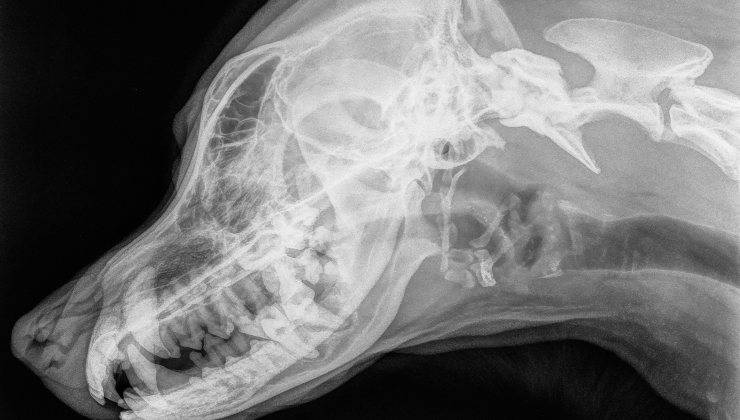

Se confrontiamo il cervello dei cani con quello dei lupi, noteremo una piccola differenza: in media, i cani tendono ad avere cervelli leggermente più piccoli rispetto a quello dei lupi.

Tuttavia, questa differenza non vale per tutte le razze canine. Come infatti, le razze canine più antiche quelle che assomigliano di più ai lupi, hanno cervelli più simili a quelli dei loro antenati selvatici. Le razze moderne invece, frutto di molti anni di selezione, presentano spesso cervelli più piccoli.

Ciò ci fa pensare che l’uomo nel corso del tempo, abbia scelto di allevare i cani con caratteristiche fisiche e comportamentali specifiche, influenzando anche lo sviluppo del loro cervello.